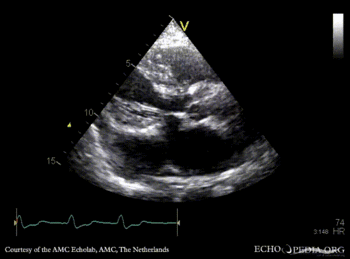

Continuous-wave Doppler signal of tricuspid regurgitation, pulmonary hypertension A4CH: dilated coronary sinus